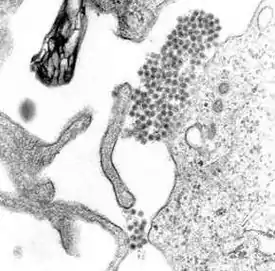

Вирусные частицы покрыты оболочкой, имеют сферическую форму и диаметр около 40—60 нм.